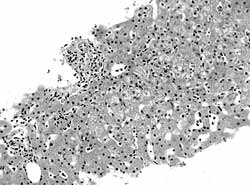

自身免疫性肝炎是由自身免疫反應引起的肝臟慢性炎症。肝組織改變與慢性病毒性肝炎相一致,但血清病毒標誌物陰性。臨床上有自身免疫的各種表現,如黃疸、發熱、皮疹、關節炎等各種症狀,並可見高γ-球蛋白血症,血沉加快,血中自身抗體陽性。